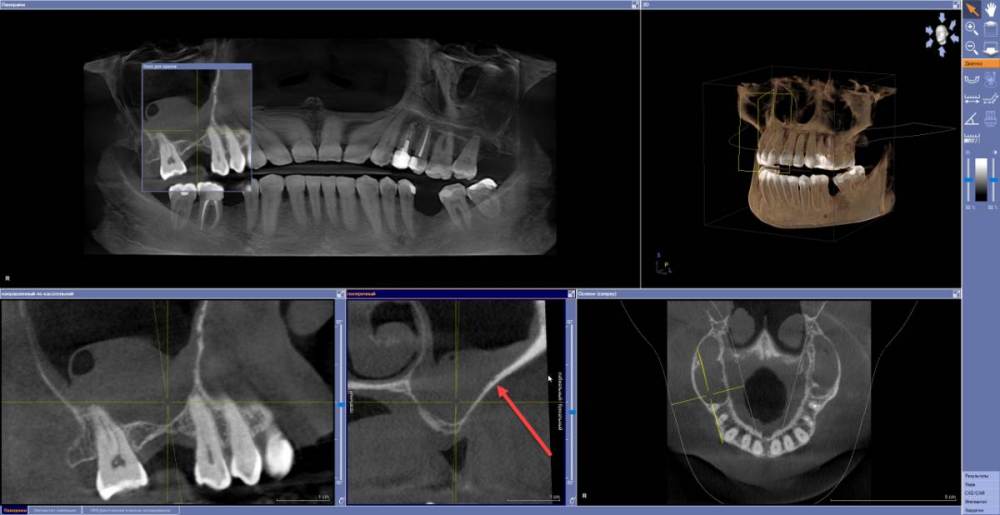

Estes Опубликовано 16 мая, 2021 Поделиться Опубликовано 16 мая, 2021 (изменено) Здравствуйте. Подошла пациентка, контактная, на позитиве. В анамнезе двусторонний синусит, пройден курс лечения у лор, типа ремиссия. Из объективного - 17, 15 зуб устойчивы. 46 зуб удален мной, нижняя челюсть - установлены импланты 46, 45, 36, курс а/б Флемоклав Солютаб 1000 по 1 таб 2р/день 6 дней. Через 2.5 месяца планируется протезирование ц/к коронками на винтовой фиксации. Пациентка хотела бы восстановить целостность зубного ряда в/ч справа имплантом. Но учитывая синусит (я так понимаю, синусит в в целом пока что непролечен), необходимость открытого синуслифтинга, отсроченной имплантациии, и вот там еще участочек, отмеченный стрелкой (есть подозрение на мелкую артерию в костной стенке) - хотел бы спросить у коллег, может лучше мостовидный протез (эндо 17 точно будет). И проводить ли эндо 15? (На всякий случай залил КТ на яндекс.диск https://disk.yandex.ru/d/xljj7uhcswkqCw в виде образа диска Галилеос в формате iso. Монтируется образ при помощи программы UltraISO в виртуальный привод) Изменено 16 мая, 2021 пользователем Estes Ссылка на комментарий

Женька Опубликовано 16 мая, 2021 Поделиться Опубликовано 16 мая, 2021 Пациентка же хочет восстановить с помощью имплантации. Эндо 1.7 с какой целью будет? Думаете проблемы в пазухе от него? Ну артерия, но кмк достаточно высоко она и в любом случае не представляет особой угрозы. Пусть более опытные коллеги меня поправят, если где-то не прав. Зачем эндо 1.5? Ссылка на комментарий

Estes Опубликовано 16 мая, 2021 Автор Поделиться Опубликовано 16 мая, 2021 (изменено) 11 минут назад, Женька сказал: Пациентка же хочет восстановить с помощью имплантации. Эндо 1.7 с какой целью будет? Думаете проблемы в пазухе от него? Ну артерия, но кмк достаточно высоко она и в любом случае не представляет особой угрозы. Пусть более опытные коллеги меня поправят, если где-то не прав. Зачем эндо 1.5? При препарировании под д/ц мостовидный протез из-за наклона 17 предполагается (но это пока что только визуально) значительное препарирование тканей мезиально - риск есть пульпита, но это пока что предположение. Проблемы в пазухе никак не от 17 "Пациентка же хочет восстановить с помощью имплантации." - Хотеть можно ,но при синусите насколько отложиться операция синуслифтинга, и пройдет ли в нашем климате (Сибирь таки ,пыльно летом и гарь постоянно) вообще этот синусит полностью - в этом есть сомнения. Изменено 16 мая, 2021 пользователем Estes Ссылка на комментарий